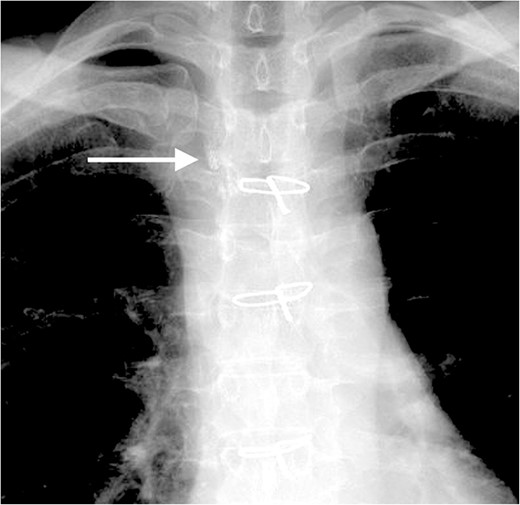

On post-operative day 17, she visited our hospital for a routine follow-up, and her chest X-ray revealed a massive right pleural effusion (Fig. 3). Therefore, she was re-admitted to our hospital and right chest drainage was performed. Milky and turbid fluid was drained with an amount of ~3100 ml. The biochemical analysis of pleural fluid revealed a triglyceride level of 1420 mg/dl, and we confirmed a diagnosis of chylothorax. She received fasting and total parenteral nutrition. The fluid via chest tubes returned to be clear with its amount of <200 ml for a day.

Chest X-ray on post-operative day 17 revealing massive pleural effusion.